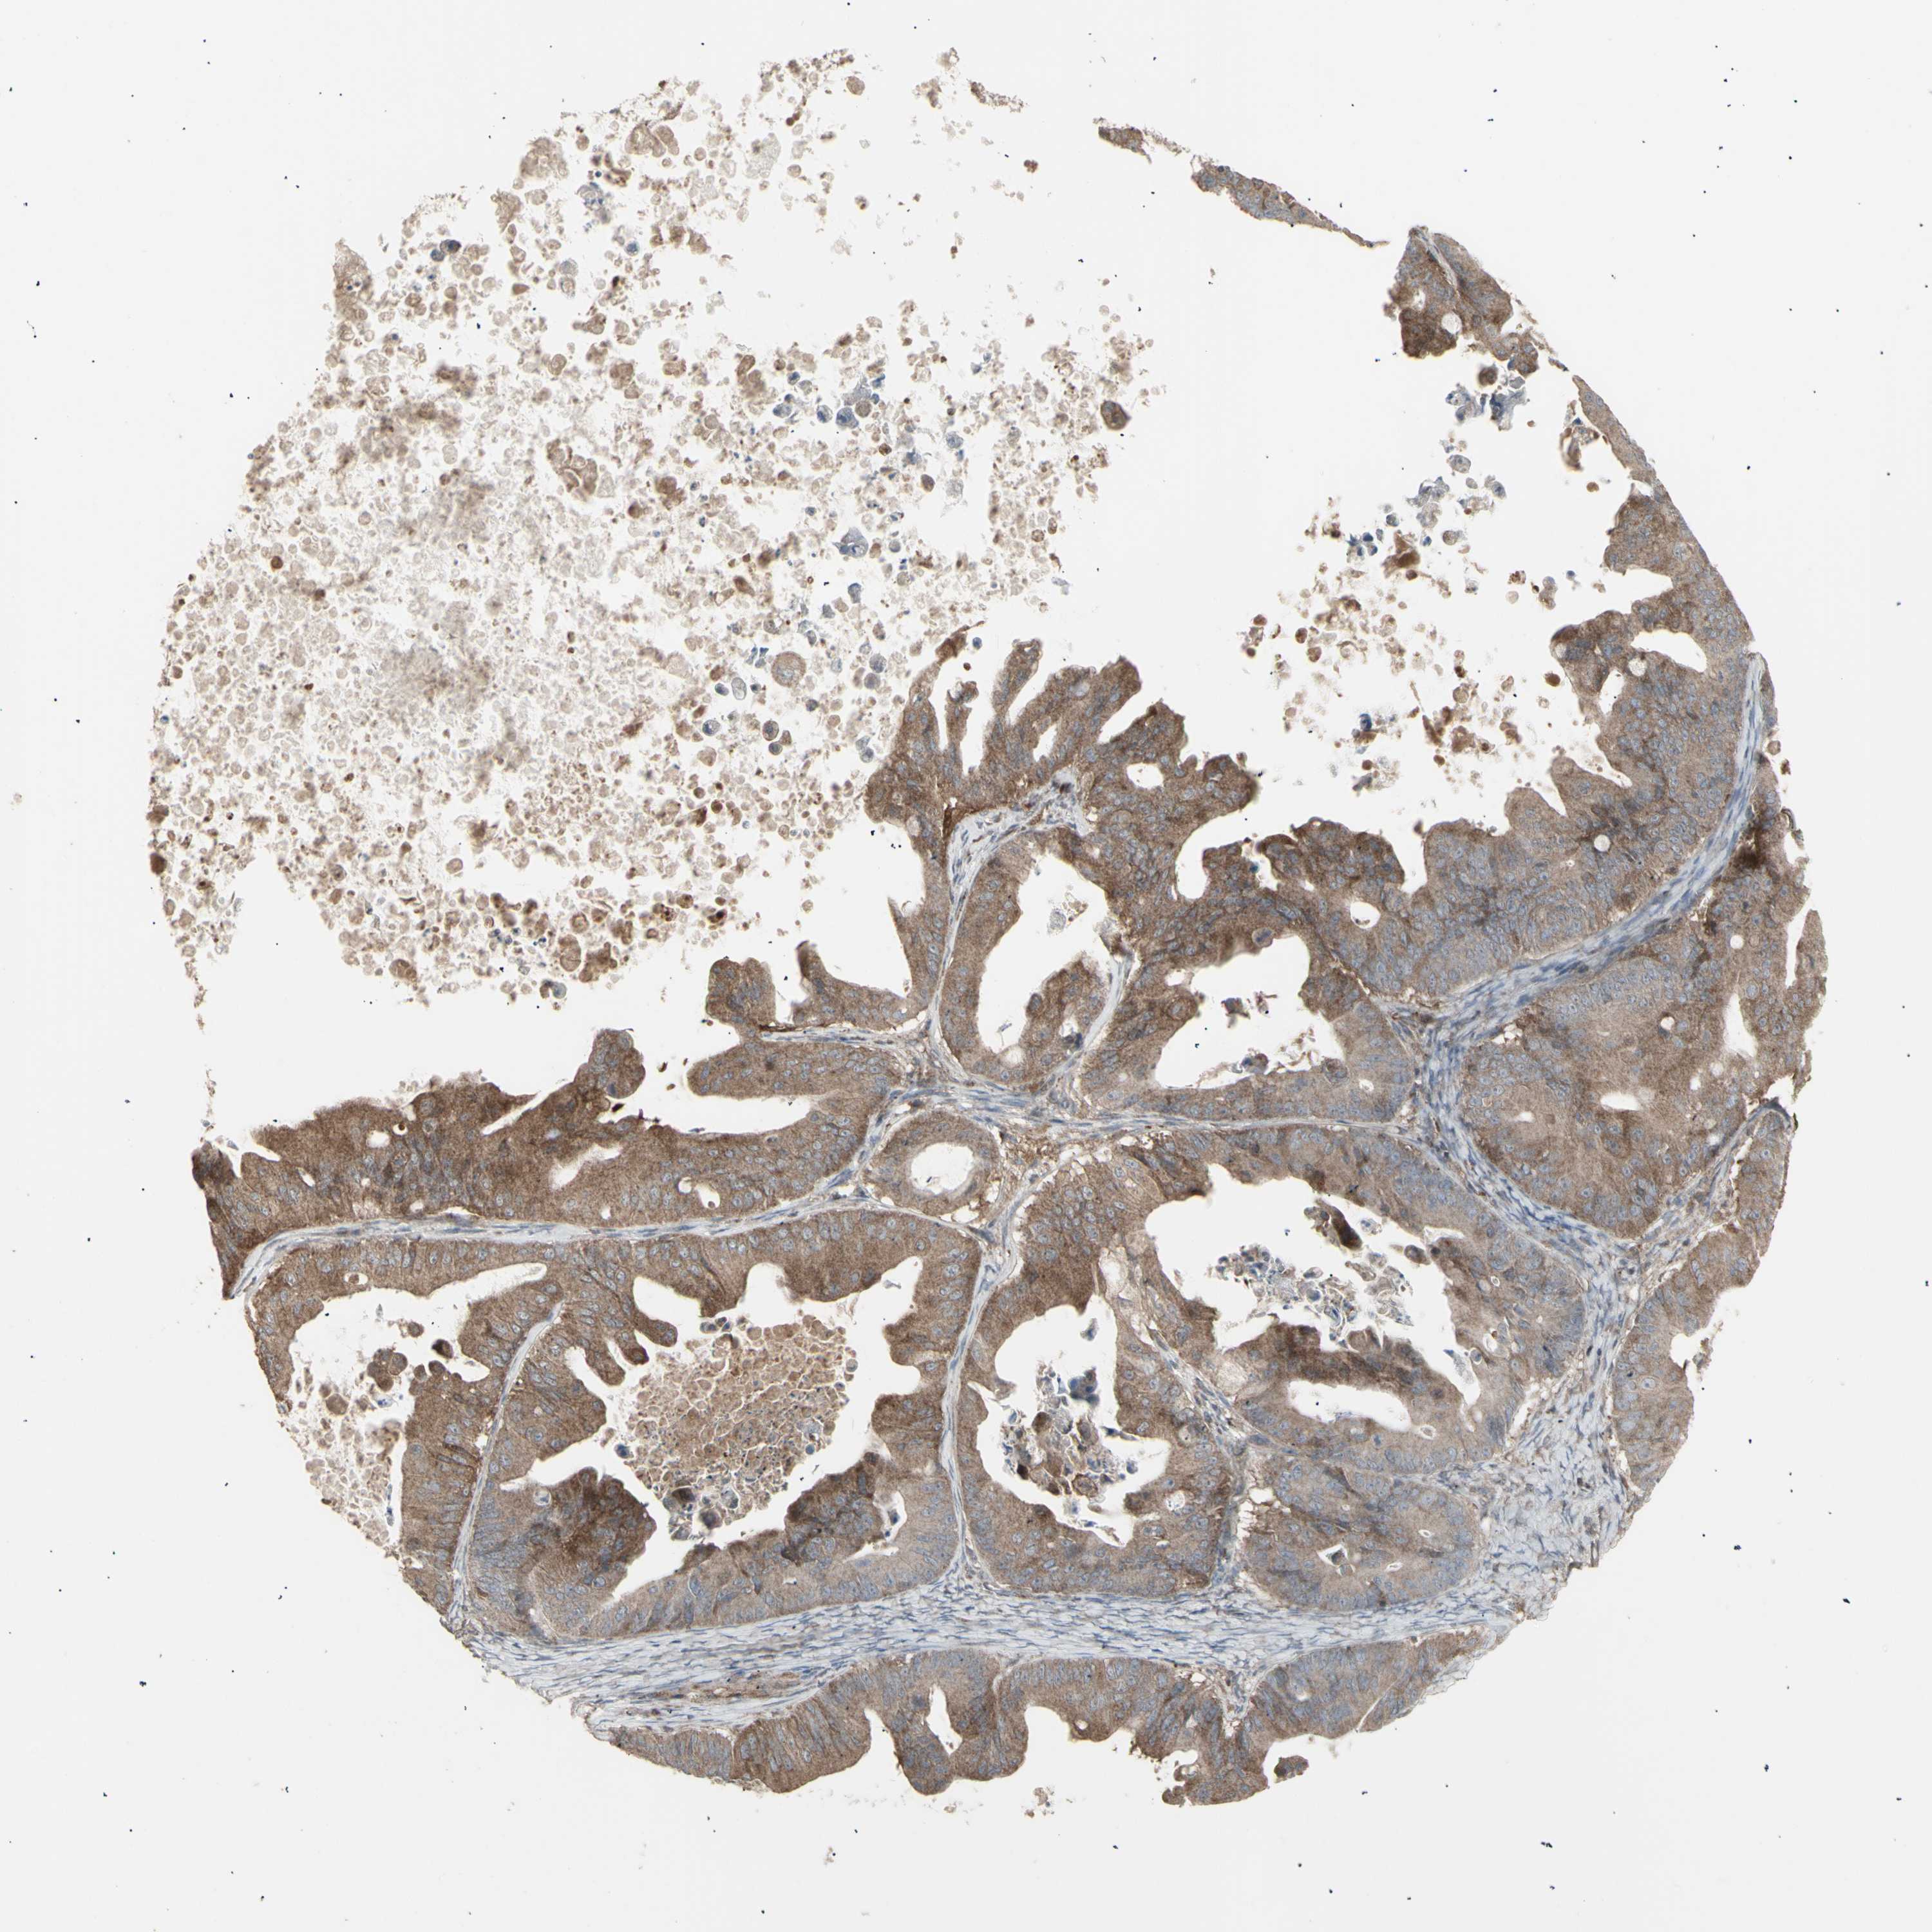

OVARIAN CANCER - Protein expressioni

A mouse-over function shows sample information and annotation data. Click on an image to view it in a full screen mode. Samples can be filtered based on level of antibody staining by selecting one or several of the following categories: high, medium, low and not detected. The assay and annotation is described here.

Note that samples used for immunohistochemistry by the Human Protein Atlas do not correspond to samples in the TCGA dataset.

Antibody stainingi

Antibody staining in the annotated cell types in the current human tissue is reported as not detected, low, medium, or high, based on conventional immunohistochemistry profiling in selected tissues. This score is based on the combination of the staining intensity and fraction of stained cells.

Each image is clickable and will lead to virtual microscopy that enables deeper exploration of all samples and also displays staining intensity scores, fraction scores and subcellular localization as well as patient and tissue information for each sample.

Antibody HPA002633

Antibody HPA046758

Antibody CAB010906

Carcinoma, endometroid

Cystadenocarcinoma, serous, NOS

Cystadenocarcinoma, mucinous, NOS

Carcinoma, NOS